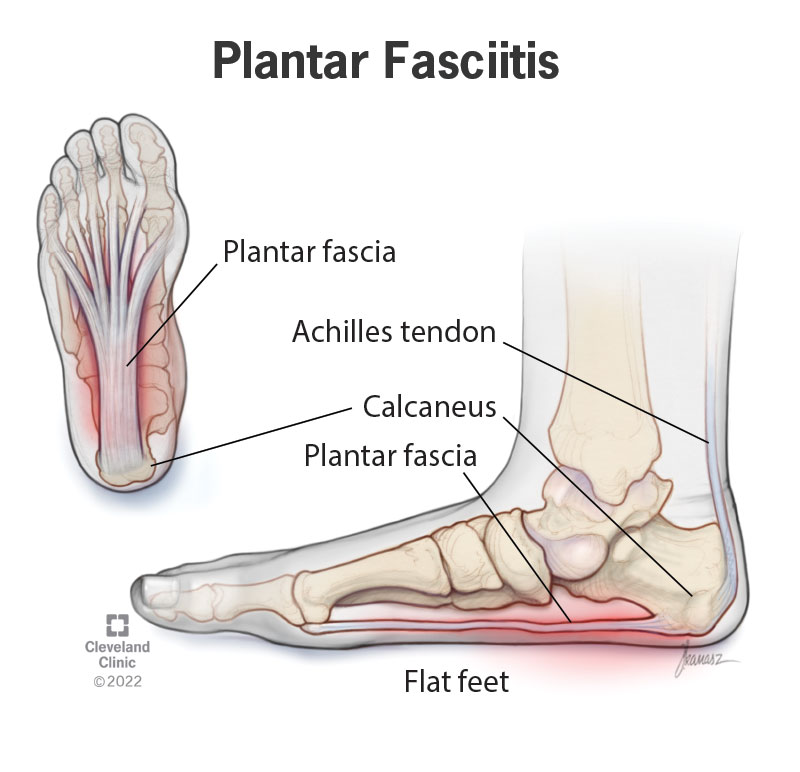

Heel Pain Causes and Treatment shop, Heel Pain Causes Diagnosis Treatment shop, 4 Heel Pain Symptoms to Take Seriously Chicagoland Foot and Ankle Board Certified Foot and Ankle Specialists and Surgeons shop, Ankle Heel Foot Pain SpinePain Solutions shop, 10 Causes of Heel Pain and When to See a Doctor Raleigh Orthopaedic shop, Heel Pain Plantar Fasciitis is a common and Painful Condition shop, Understanding Foot Pain Foot Pain Chart Foot Pain Diagram Pain Medicine Consultants Pain Specialists shop, Pain In The Back Of The Heel What Could It Mean shop, Pain In The Back Of The Heel What Could It Mean shop, Main Causes of Back of Heel Pain in North Seattle Foot and Ankle Center of Lake City shop, What Causes Heel Pain shop, Not all heel pain is Plantar Fasciitis RunningPhysio shop, Common Conditions Causing Heel Pain shop, Common Causes of Pain in the Back of the Ankles Pain Management NYC shop, Plantar Fasciitis Foot and Ankle Specialists shop, Diagnosis of Heel Pain AAFP shop, Heel pain s latest treatment techniques A Step Ahead Foot and Ankle Care shop, Ankle Heel Pain Treatment Specialists DPMC shop, Heel Pain Causes Treatment Prevention Podiatry Sydney shop, Medial Ankle Pain Tarsal Tunnel Syndrome Sports Injury Physio shop, A Stabbing Heel Pain shop, Foot Pain Conditions Causes Symptoms Treatments HSS shop, Pinpoint Your Foot Ankle Pain OrthoNebraska shop, What is heel pain Sole Podiatry shop, Foot and Ankle Pain Treatment in New Jersey RWJBarnabas Health shop, Heel Pain Causes Diagnosis and Treatment Options Joint Replacement Institute shop, Severs Disease Sever s Disease Treatment Sydney shop, Plantar Fasciitis Symptoms Causes Treatment Options shop, Ankle Pain and Plantar Fasciitis Treatment Softwave Clinics shop, Side Heel Pain What You Should Know Cellaxys shop, Foot Pain Conditions Causes Symptoms Treatments HSS shop, Effective Treatment for Heel Pain Foot Foundation shop, Heel Pain Podiatrist in Old Bridge and Sayreville NJ Jason Grossman DPM shop, Foot and Ankle Pain Treatment in Schertz BioMotion PT shop, Achilles Tendinopathy Causes Symptoms Treatment The Feet People Podiatry shop.